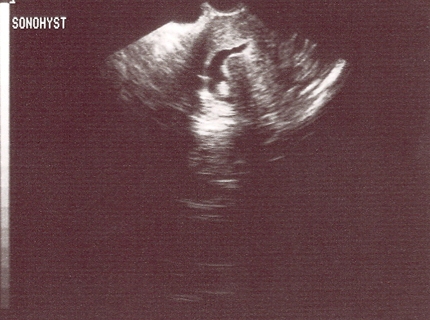

sonohysterography

High sensitivity for the detection of submucous and intramural fibroids.[43][51] For intracavitary lesions detected by transvaginal ultrasound, the biggest challenge is in differentiating endometrial polyps from submucous uterine fibroids; both are space-occupying intracavitary lesions. It is important to keep in mind that endometrial polyps are completely intraluminal in location and can be seen to freely move during injection of saline. [Figure caption and citation for the preceding image starts]: Sonohysterography shows several small intracavitary masses suspicious for polypsFrom the personal collection of Dr M.F. Mitwally and Dr R.J. Fischer; used with permission [Citation ends].

Fibroids are generally less echogenic than polyps and surrounding endometrium and careful examination can frequently reveal continuity with the surrounding myometrium.[53][Figure caption and citation for the preceding image starts]: Sonohysterography demonstrates a posterior submucous uterine fibroid deforming the posterior endometrial cavityFrom the personal collection of Dr M.F. Mitwally and Dr R.J. Fischer; used with permission [Citation ends].

Result

intramural and subserosal uterine fibroids; diagnostic criteria similar to that used for transvaginal and transabdominal ultrasound diagnosis